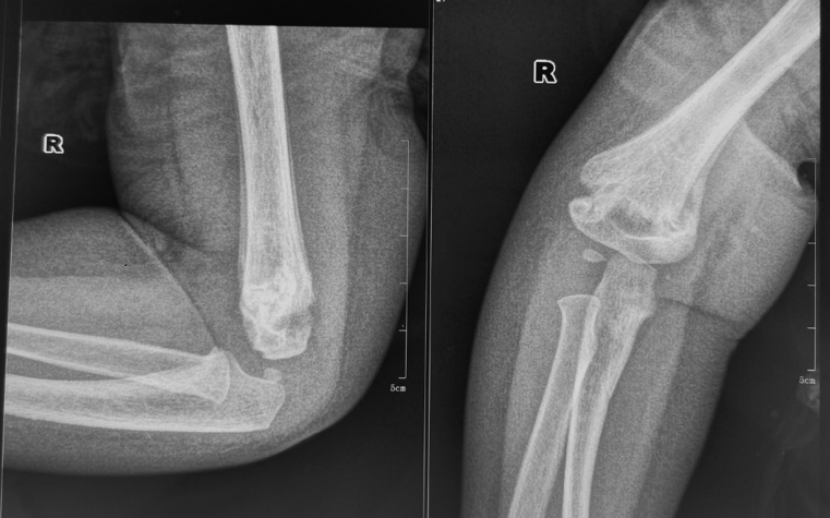

病例3:小玉(化名)、女、4岁,2年前因摔伤致“右肱骨髁上骨折”,于当地医院行手法复位石膏外固定,石膏固定一个月拆除外固定后逐渐发生右肘内翻畸形。

拆除石膏后X线片

该患者的情况跟小红的一样,都是治疗不规范引起的肘内翻畸形。该病例虽然年龄较小,但肘内翻畸形严重,保守治疗2年后未见明显改善,遂于行手术治疗。

术后X线片

取完钢针后随访